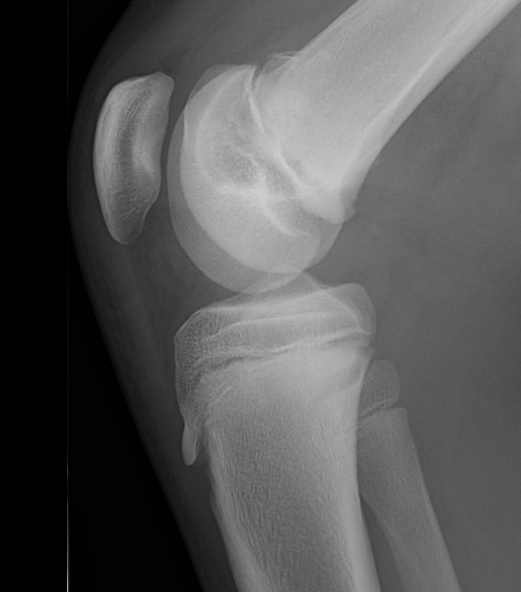

Salter Harris I

Salter Harris II